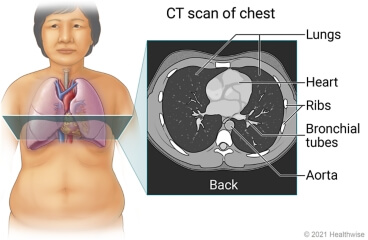

Що таке комп'ютерна томографія?

КТ – це неінвазивний медичний тест на візуалізацію, який використовує рентгенівські промені та комп'ютерні технології для отримання детальних зображень внутрішніх структур в організмі. Під час КТ пацієнт лежить на столі, який всувається в апарат, що робить кілька рентгенівських знімків тіла під різними кутами. Потім комп'ютер обробляє ці зображення, щоб створити детальне 3D-зображення внутрішніх структур.